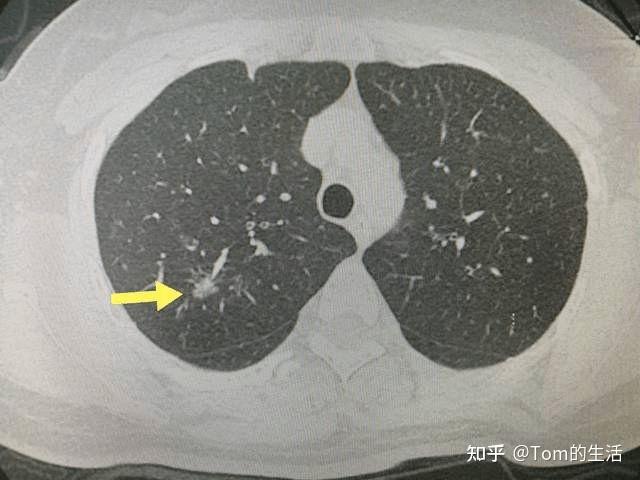

左下肺背段见分叶状结节影,会是什么?